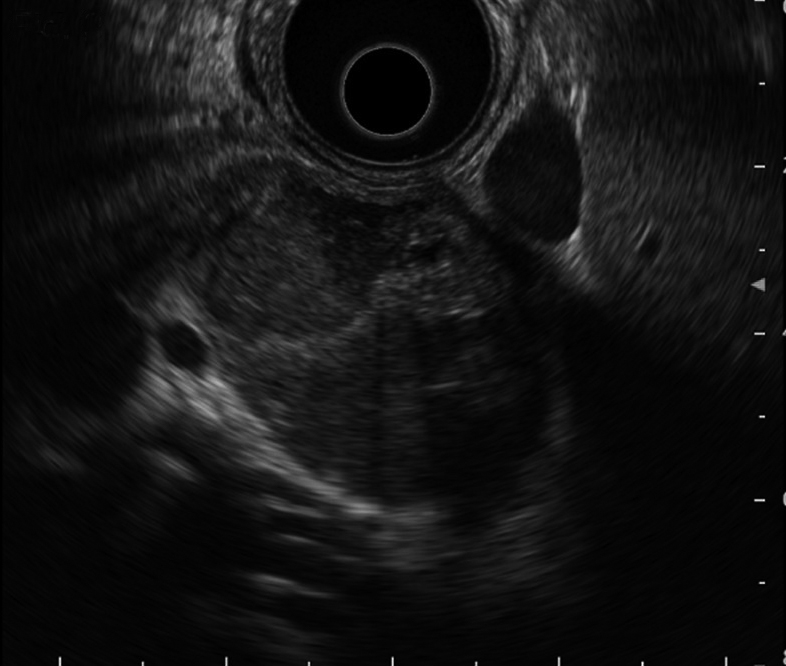

超音波内視鏡検査所見:腫瘤内に多房状構造,隔壁様構造を認めた.低エコー域内に出血を示唆する等~高エコー領域を認めた(Fig. 3).

Endoscopic US showing multilocular cystic lesion with septations. Hyper echoic area can be observed in the cyst.